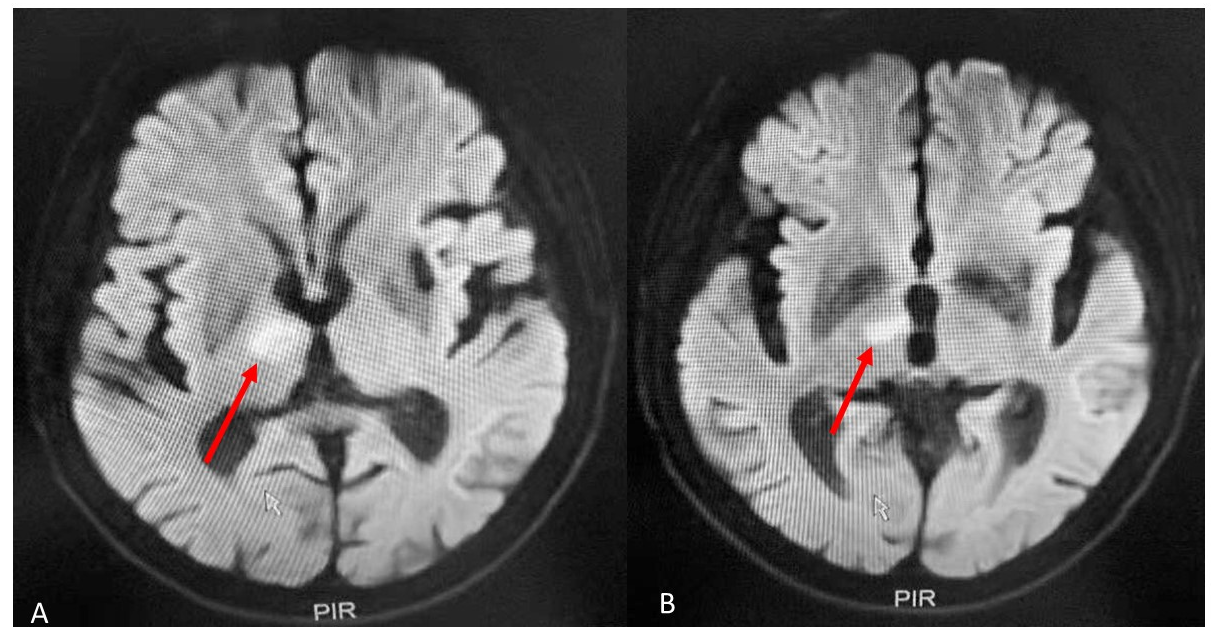

MRI of the brain revealed an infarct in the right thalamus confined to the anterior region (Figure 1 A & B). The hippocampi showed bilateral preserved in volume. EEG was normal. Blood workup showed no abnormalities.

Figure 1 T2 weighted MRI showing an infarct located in the right anterior nucleus of thalamus (red arrows) (A & B).